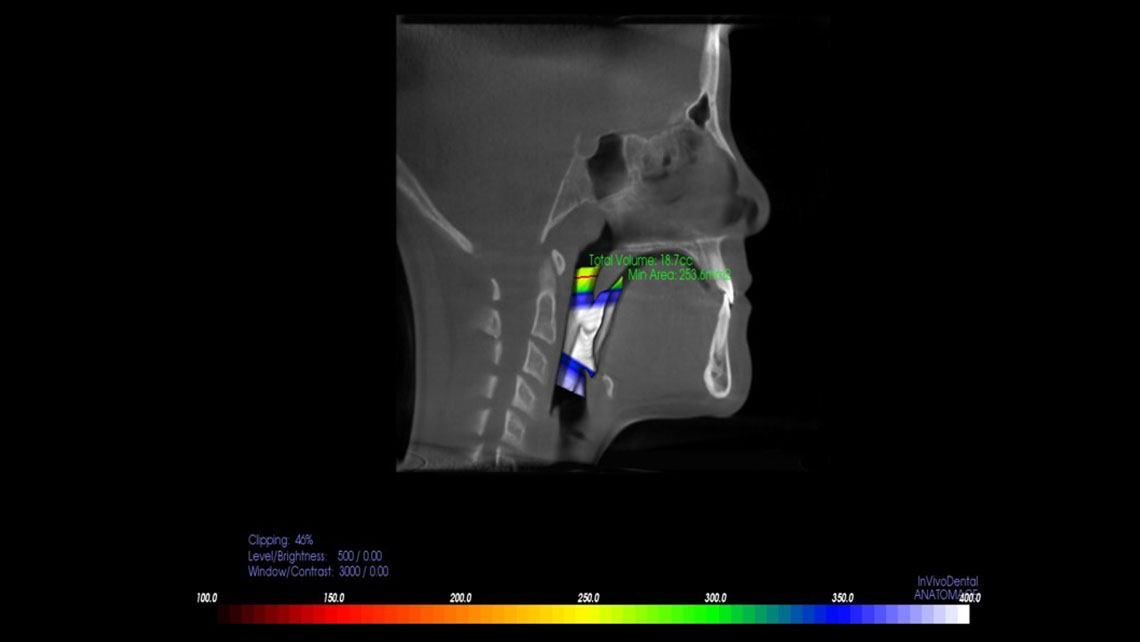

TMJ, Sleep Therapy & Airway Orthodontics utilizes the most advanced technology available. Our i-CAT® FLX Cone Beam 3D system is designed to provide greater flexibility in scanning, planning, and treatment. This latest advancement of our award-winning technology offers a range of innovative features that deliver increased clarity, ease-of-use, and control.

The i-CAT® FLX offers the most flexible imaging control of any cone beam 3D unit, allowing Dr. Walker to target the desired field-of-view on each patient while minimizing the dose. With i-CAT® FLX, Dr. Walker can customize scanning options for greater control of the field-of-view, dose and resolution for a perfect image.